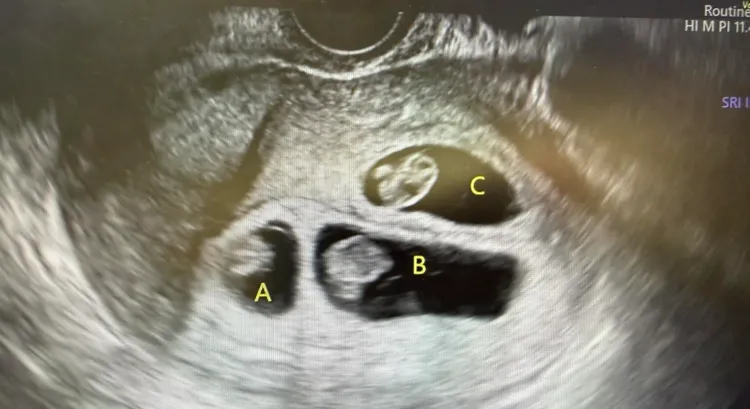

張至婷發文表示,「排卵藥吃出DoReMi,我都要哭了」,她也在留言區補充解釋,自己是這個個案的生殖科醫師,不過個案真的很年輕、也非常幸運,僅僅吃了五天排卵藥,沒有打任何促排針,就長出3顆卵泡、3顆都中獎。

她表示「看到新的小生命,大家都會忍不住開心、充滿期待,我也會把這份祝福轉送給這對爸媽」,不過身為婦產科醫師,她還是要提醒,雖然一次「進度超前」很令人驚喜,但多胞胎懷孕對媽媽的身體仍是很大的負擔,因此她還是鼓勵一次一個,「健康平安,就是最好的安排」。